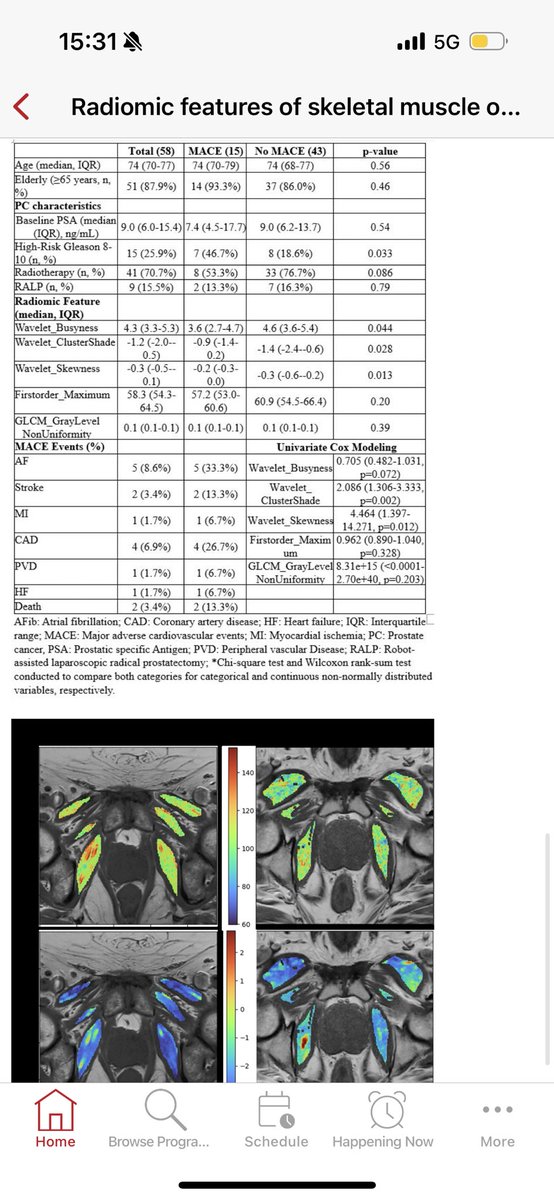

Finally ending the day with moderated poster by @DocHariKris who is presenting work we did with @anantm @RakeSHiradkar from @CoulterBME @EmoryAIHumanity: Radiomic features of skeletal muscle on prostate T1-Weighted MRI associated with MACE outcomes in prostate cancer patients undergoing hormonal therapy @sagarapatel @GACancerCenterImage

Image